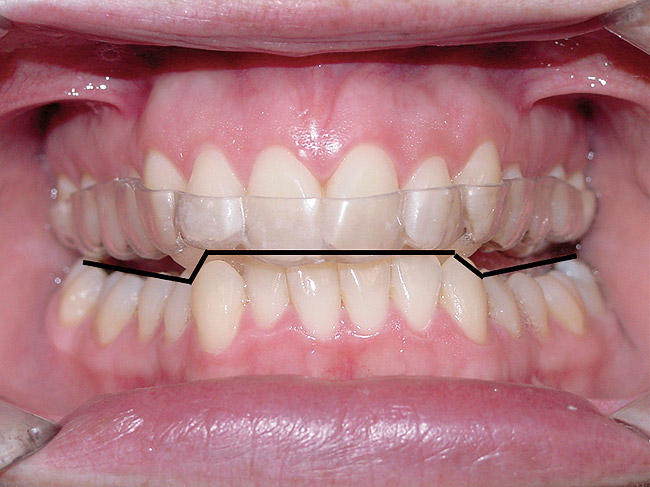

Figure 4  Palatally inclined upper central incisors  indicating a negative torque. In this situation the first  point of contact upon closure occurs in these teeth  leading (Occlusal Fence I) to a posterior shift and  distalization of the mandible.

Figure 4

Figure 5  After orthodontic correction, the upper  central incisors have a positive torque, and the posterior  shift of the mandible on closure is eliminated.

Figure 5

Figure 8  This case shows the shift of the  mandible from the point of first contact to full  closure because of the anterior restriction, which  has caused the mandible to shift posteriorly and  to the left. This patient experienced symptoms  of right lateral pterygoid tenderness with left  TMJ pain, left-sided headaches, and neck stiffness.  Release of this restriction allowed the  mandible to reposition itself to the midline with  reduction of the symptoms.

Figure 8